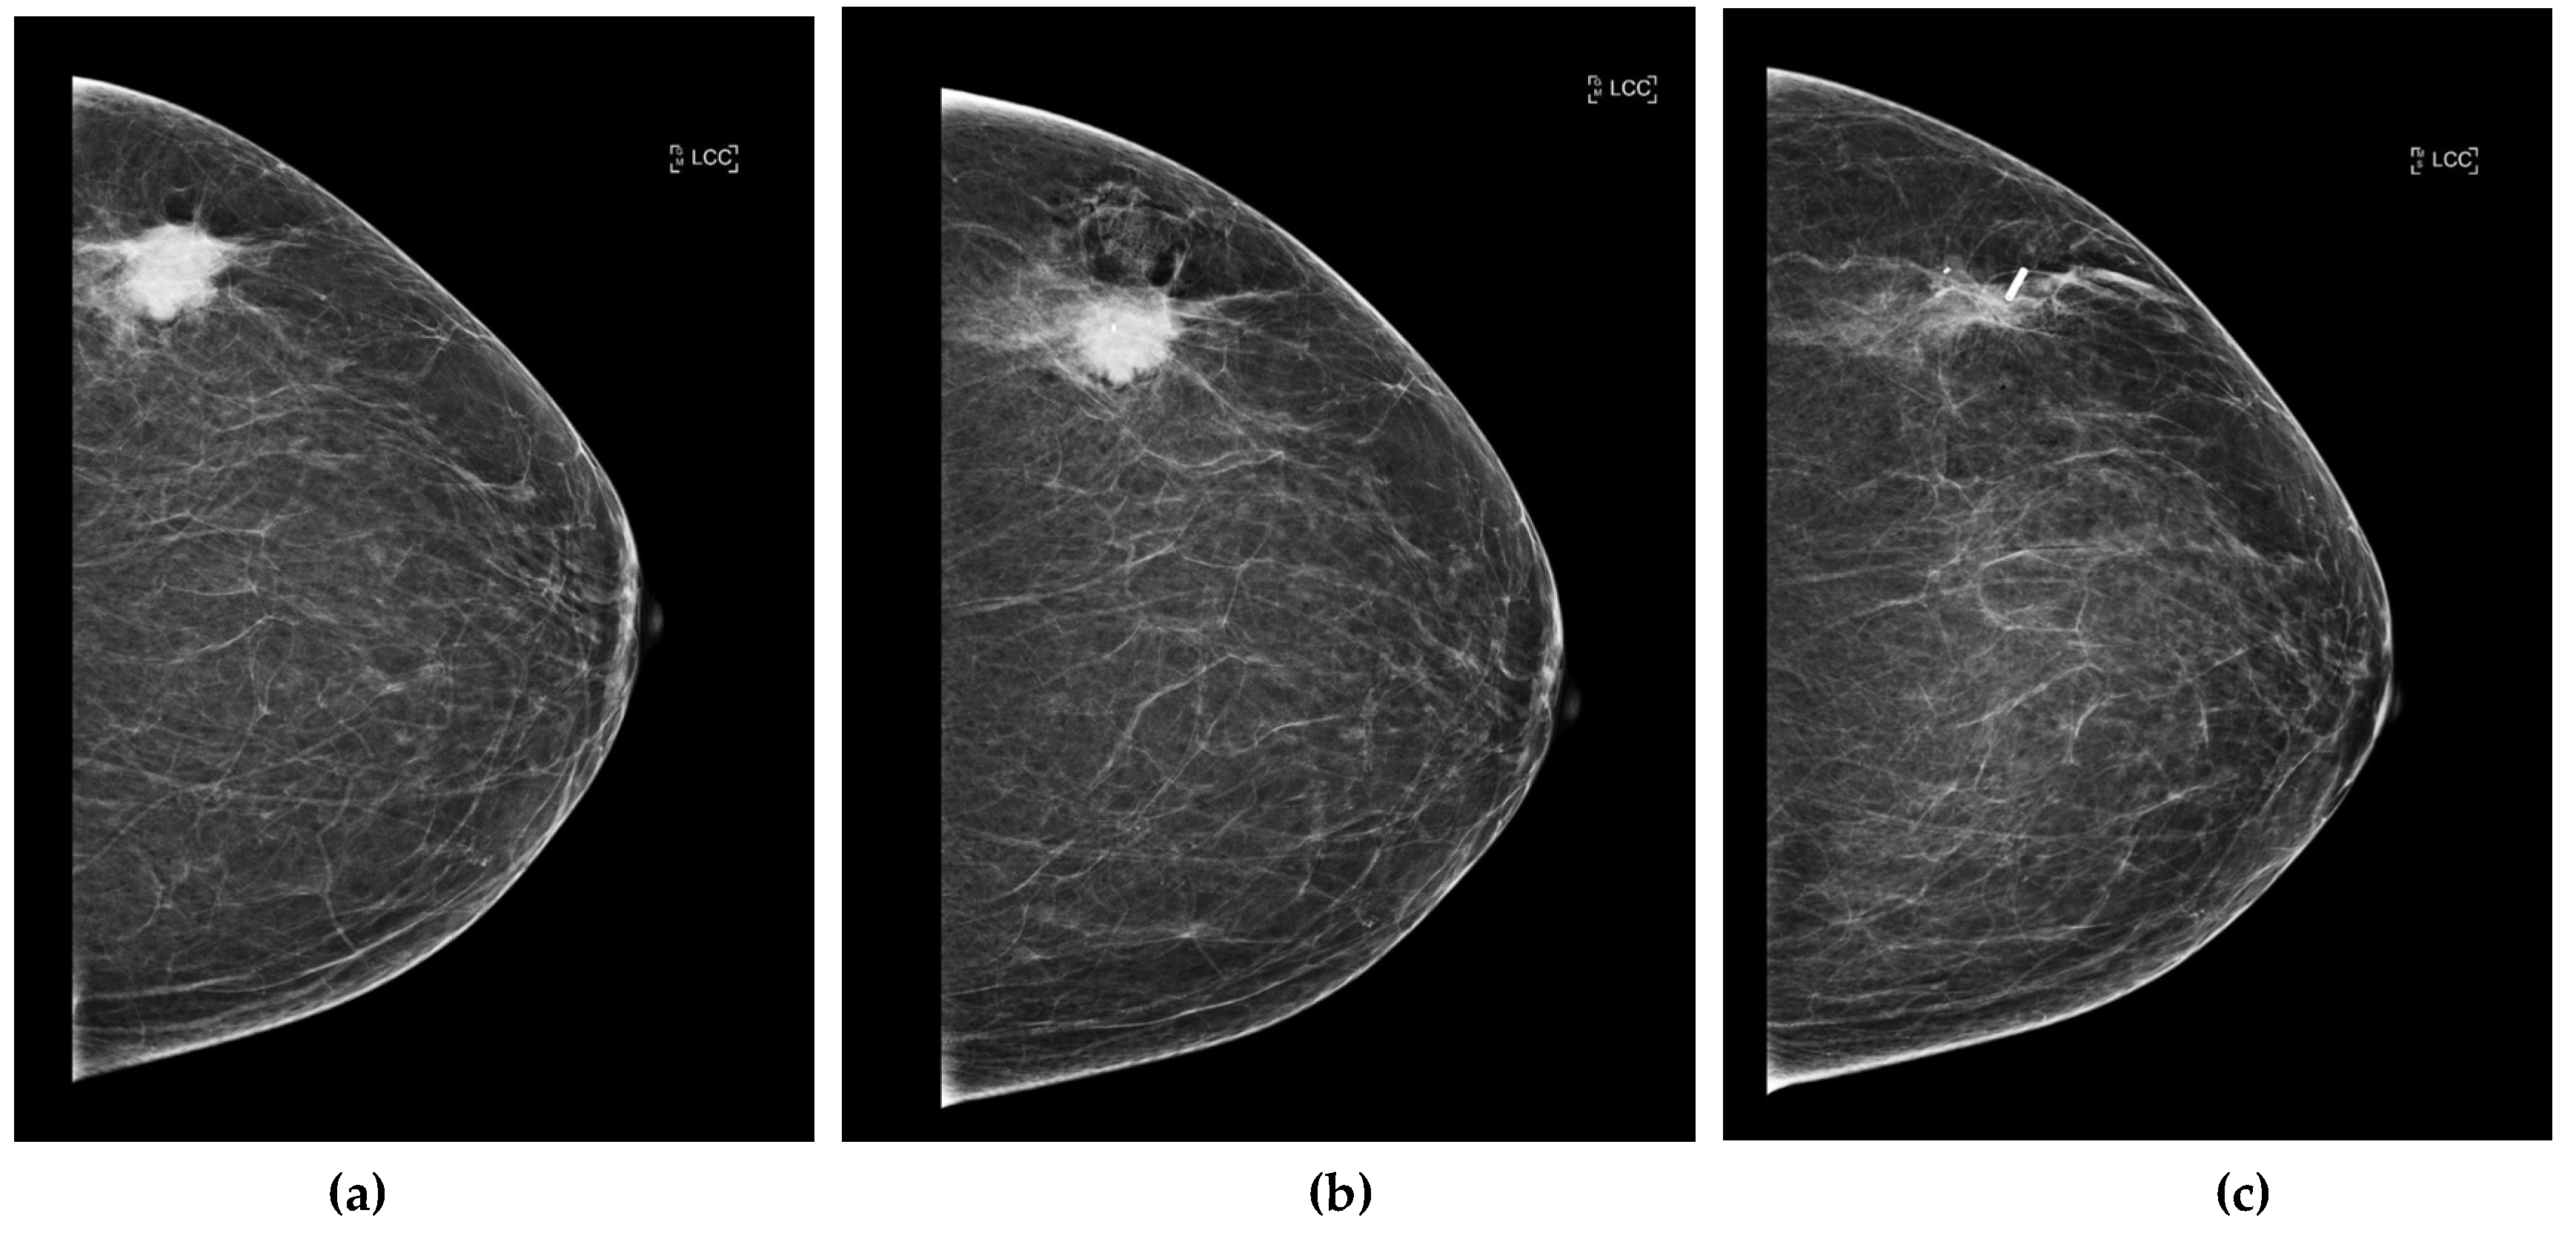

Post-placement, standard two-view mammograms were obtained to confirm tag placement. Placement accuracy was recorded by measuring the shortest distance, on either the mediolateral oblique (MLO) or craniocaudal (CC) view, from the tag to the intended target (e.g., target lesion, distortion, MCC) on the post-clip mammograms. Following surgical excision, a specimen radiograph was performed to confirm tag presence and location (Figure 3a, 3b, 3c, and 4). Additionally, any cases of tag migration were documented, along with factors such as hematoma formation or lesion characteristics that may have influenced tag positioning. Data collection was conducted in compliance with institutional ethical guidelines, ensuring patient confidentiality and adherence to research standards.

Figure 3. (a) Craniocaudal (CC) view of the left breast of predominately fat density (BI-RADS A). There is a 27 mm malignant appearing mass in the upper portion of the left breast. (b) CC post-biopsy mammogram shows the marker clip within the centre of the lesion. Following ultrasound-guided core needle biopsy and accurate clip placement, biopsy results yielded invasive ductal carcinoma (grade 3). The patient underwent neo-adjuvant chemotherapy followed by radiofrequency tag localisation. (c) CC view of the left breast. The known mass within the upper outer quadrant has reduced in size following neo-adjuvant chemotherapy and measures 19mm (from 27mm initially). The post-localisation mammogram shows successful tag placement (at the lateral aspect of the lesion). .